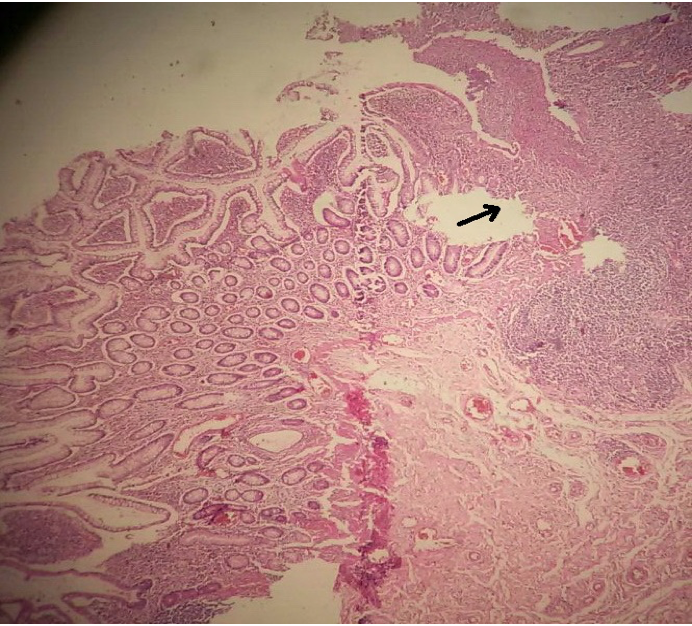

Figure 1 The ileo-caecal resection specimen: The ileal mucosa shows dense inflammatory infiltrate (arrow) (H&E, low magnification).